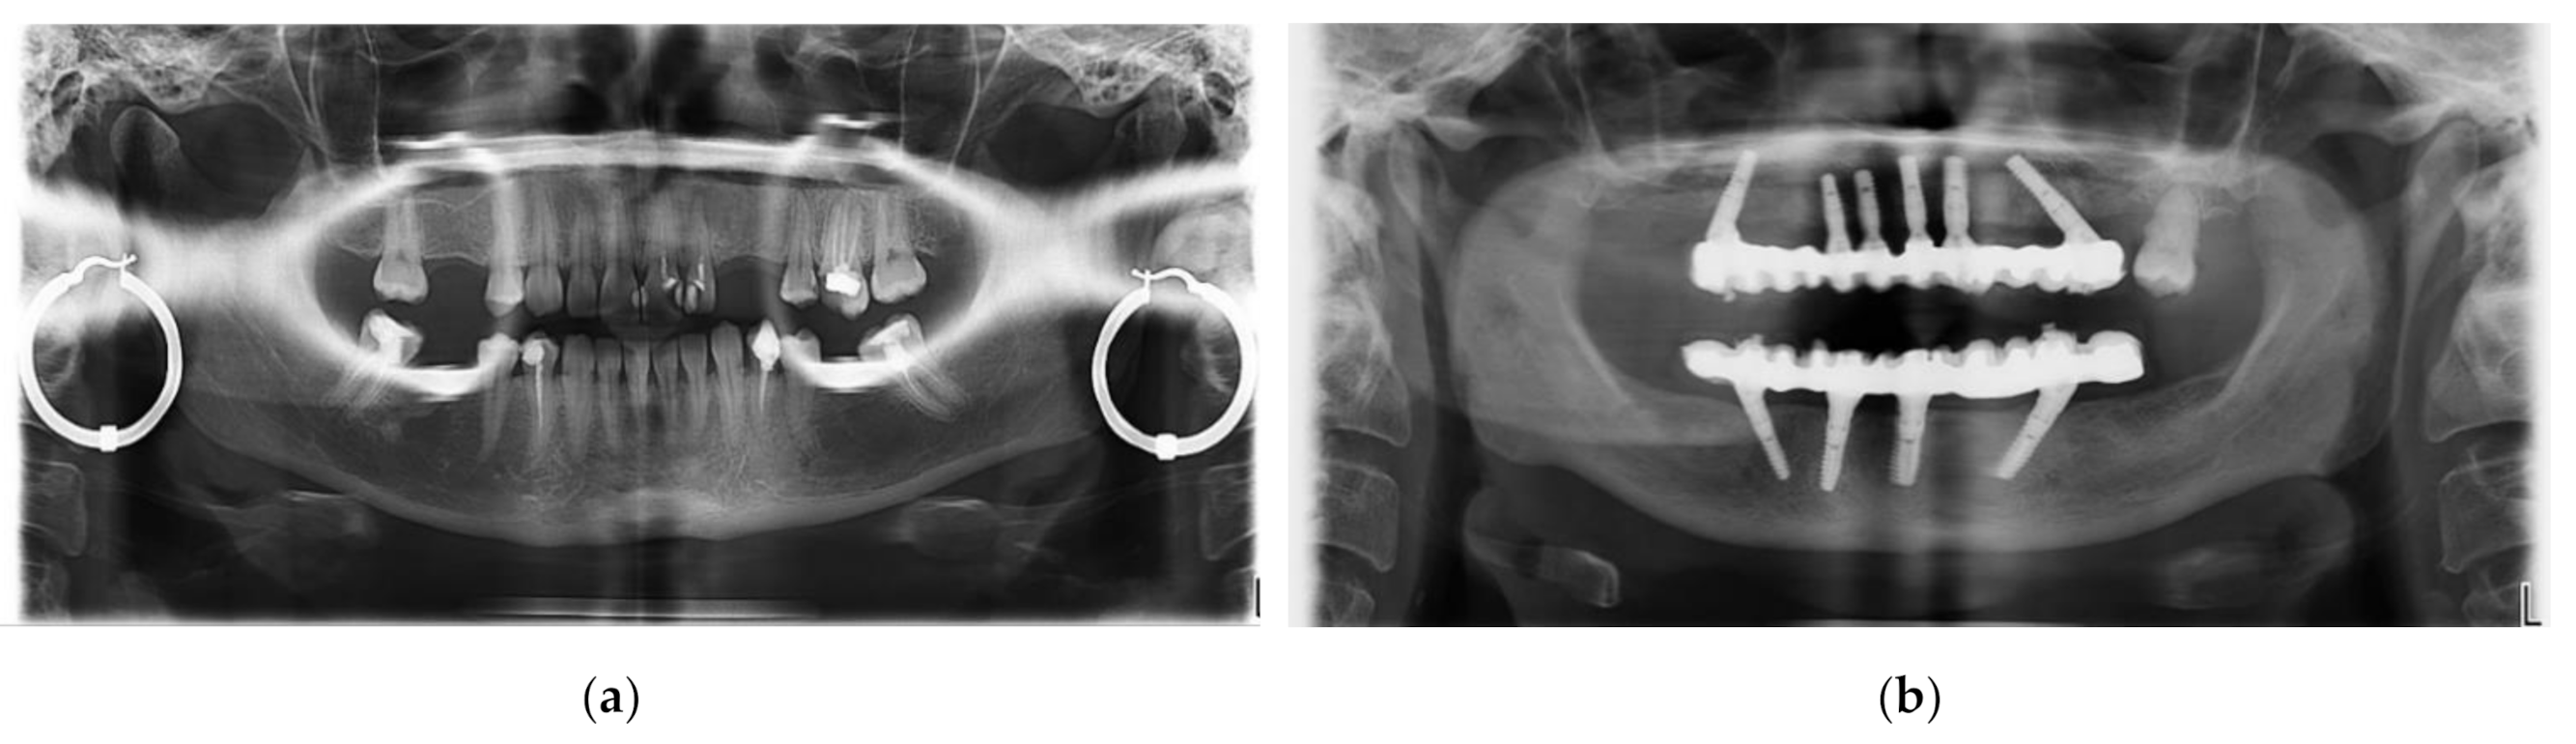

- (4)

- Jewelry or any metal around the head or neck must be taken off, otherwise artifacts may appear on radiographs (Figure 17a). This is a general requirement, irrespective of the calibration procedure using OCT. On the other hand, implants and some materials used for dental crowns or dental fillings do not produce artifacts or sparkles around them on radiographs, as shown in the example in Figure 17b. This latter aspect must be considered during calibrations.